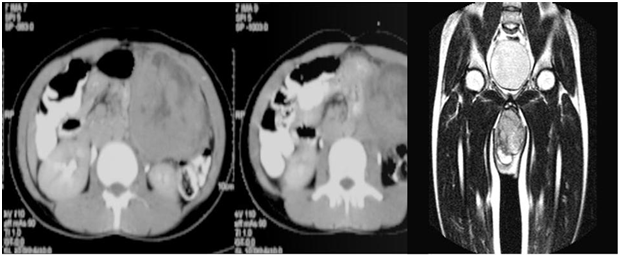

Figure 5 STIR coronal sequences of the pelvis, MRI images showing a heterogeneously hyperintense mass in the pelvis arising from the acetabulum.

Figure 6 MRI of the foot, sagittal STIR sequence showing a heterogeneous mass involving the fore and mid foot.

Figure 7MRI of the hand, STIR images showing a hypointense mass arising from the thumb

Figure 8 Contrast enhanced, CT coronal sections showing a heterogeneous mass arising from the right mandible.

Figure 9 Contrast enhanced axial CT sections of abdomen showing a heterogeneous mass in the right para-spinal region.